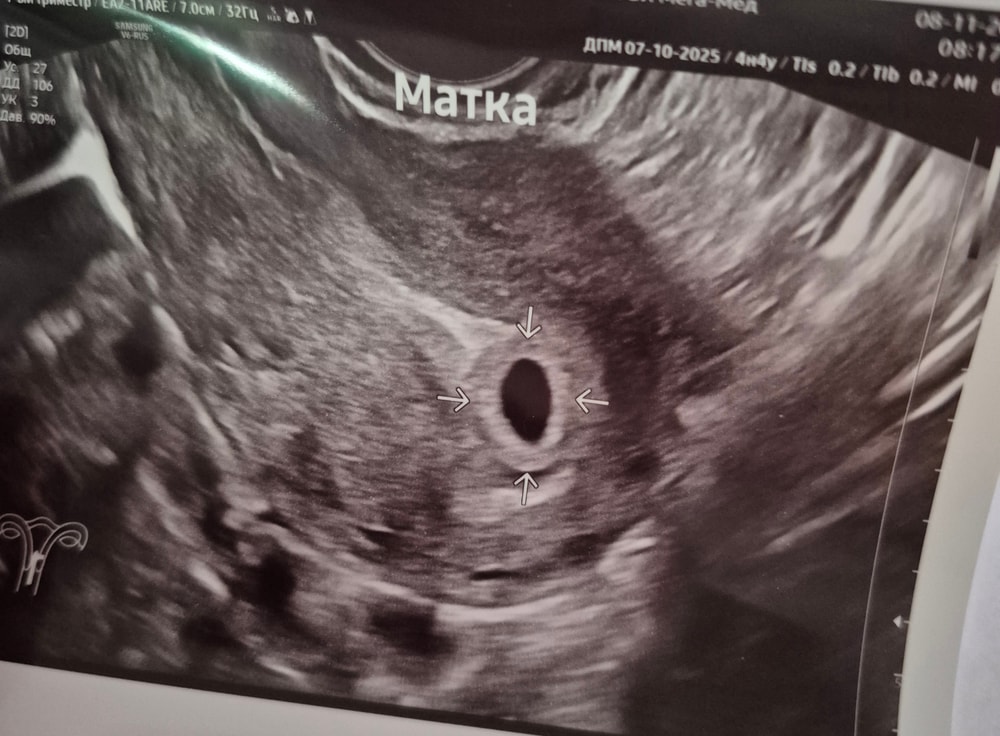

УЗИ, КТГ, доплерРешила все-таки сходить на узи и убедиться , что беременность маточная. Поставили срок 4-5 недель. Сказали, что есть маленькая совсем гематома . Через 2 недели на повторное узи, чтоб увидеть эмбрион и сердечко послушать 🙏

Решила все-таки сходить на узи и убедиться , что беременность маточная. Поставили срок 4-5 недель. Сказали, что есть маленькая совсем гематома . Через 2 недели на повторное узи, чтоб увидеть эмбрион и сердечко послушать 🙏